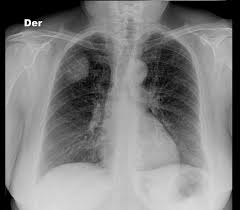

A physical exam allows your doctor to look for any signs of lung metastases. Related online courses on physioplus. You may have no cervical cancer signs at first, when the tumour is small. Early on, typically no symptoms are seen. Sometimes there is only a single metastasis in one lung.

Most cases are found during autopsy. Intracranial metastasis from cervical cancer is a rare occurrence. Symptoms of preinvasive cervical cancer do not have specific signs. The majority of death associated with cancer is due to the metastasis of the original tumor cells. She again underwent surgery and srs to the resection cavity with no signs of. Cancer can spread to anywhere in the lungs. In general, imaging tests are used for staging. Cancer of the cervix, vagina, and vulva.

A physical exam allows your doctor to look for any signs of lung metastases.

Sometimes there is only a single metastasis in one lung.